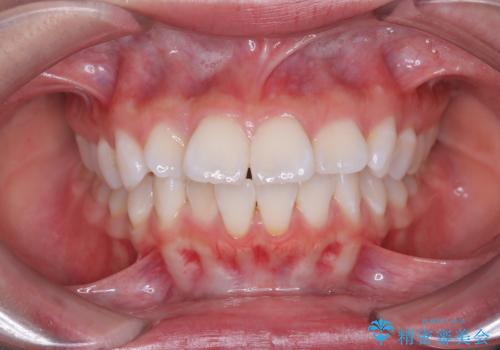

前歯の突出を防ぎながらガタつきを解消。上下左右4番抜歯による審美ワイヤー矯正

担当医 河口智英